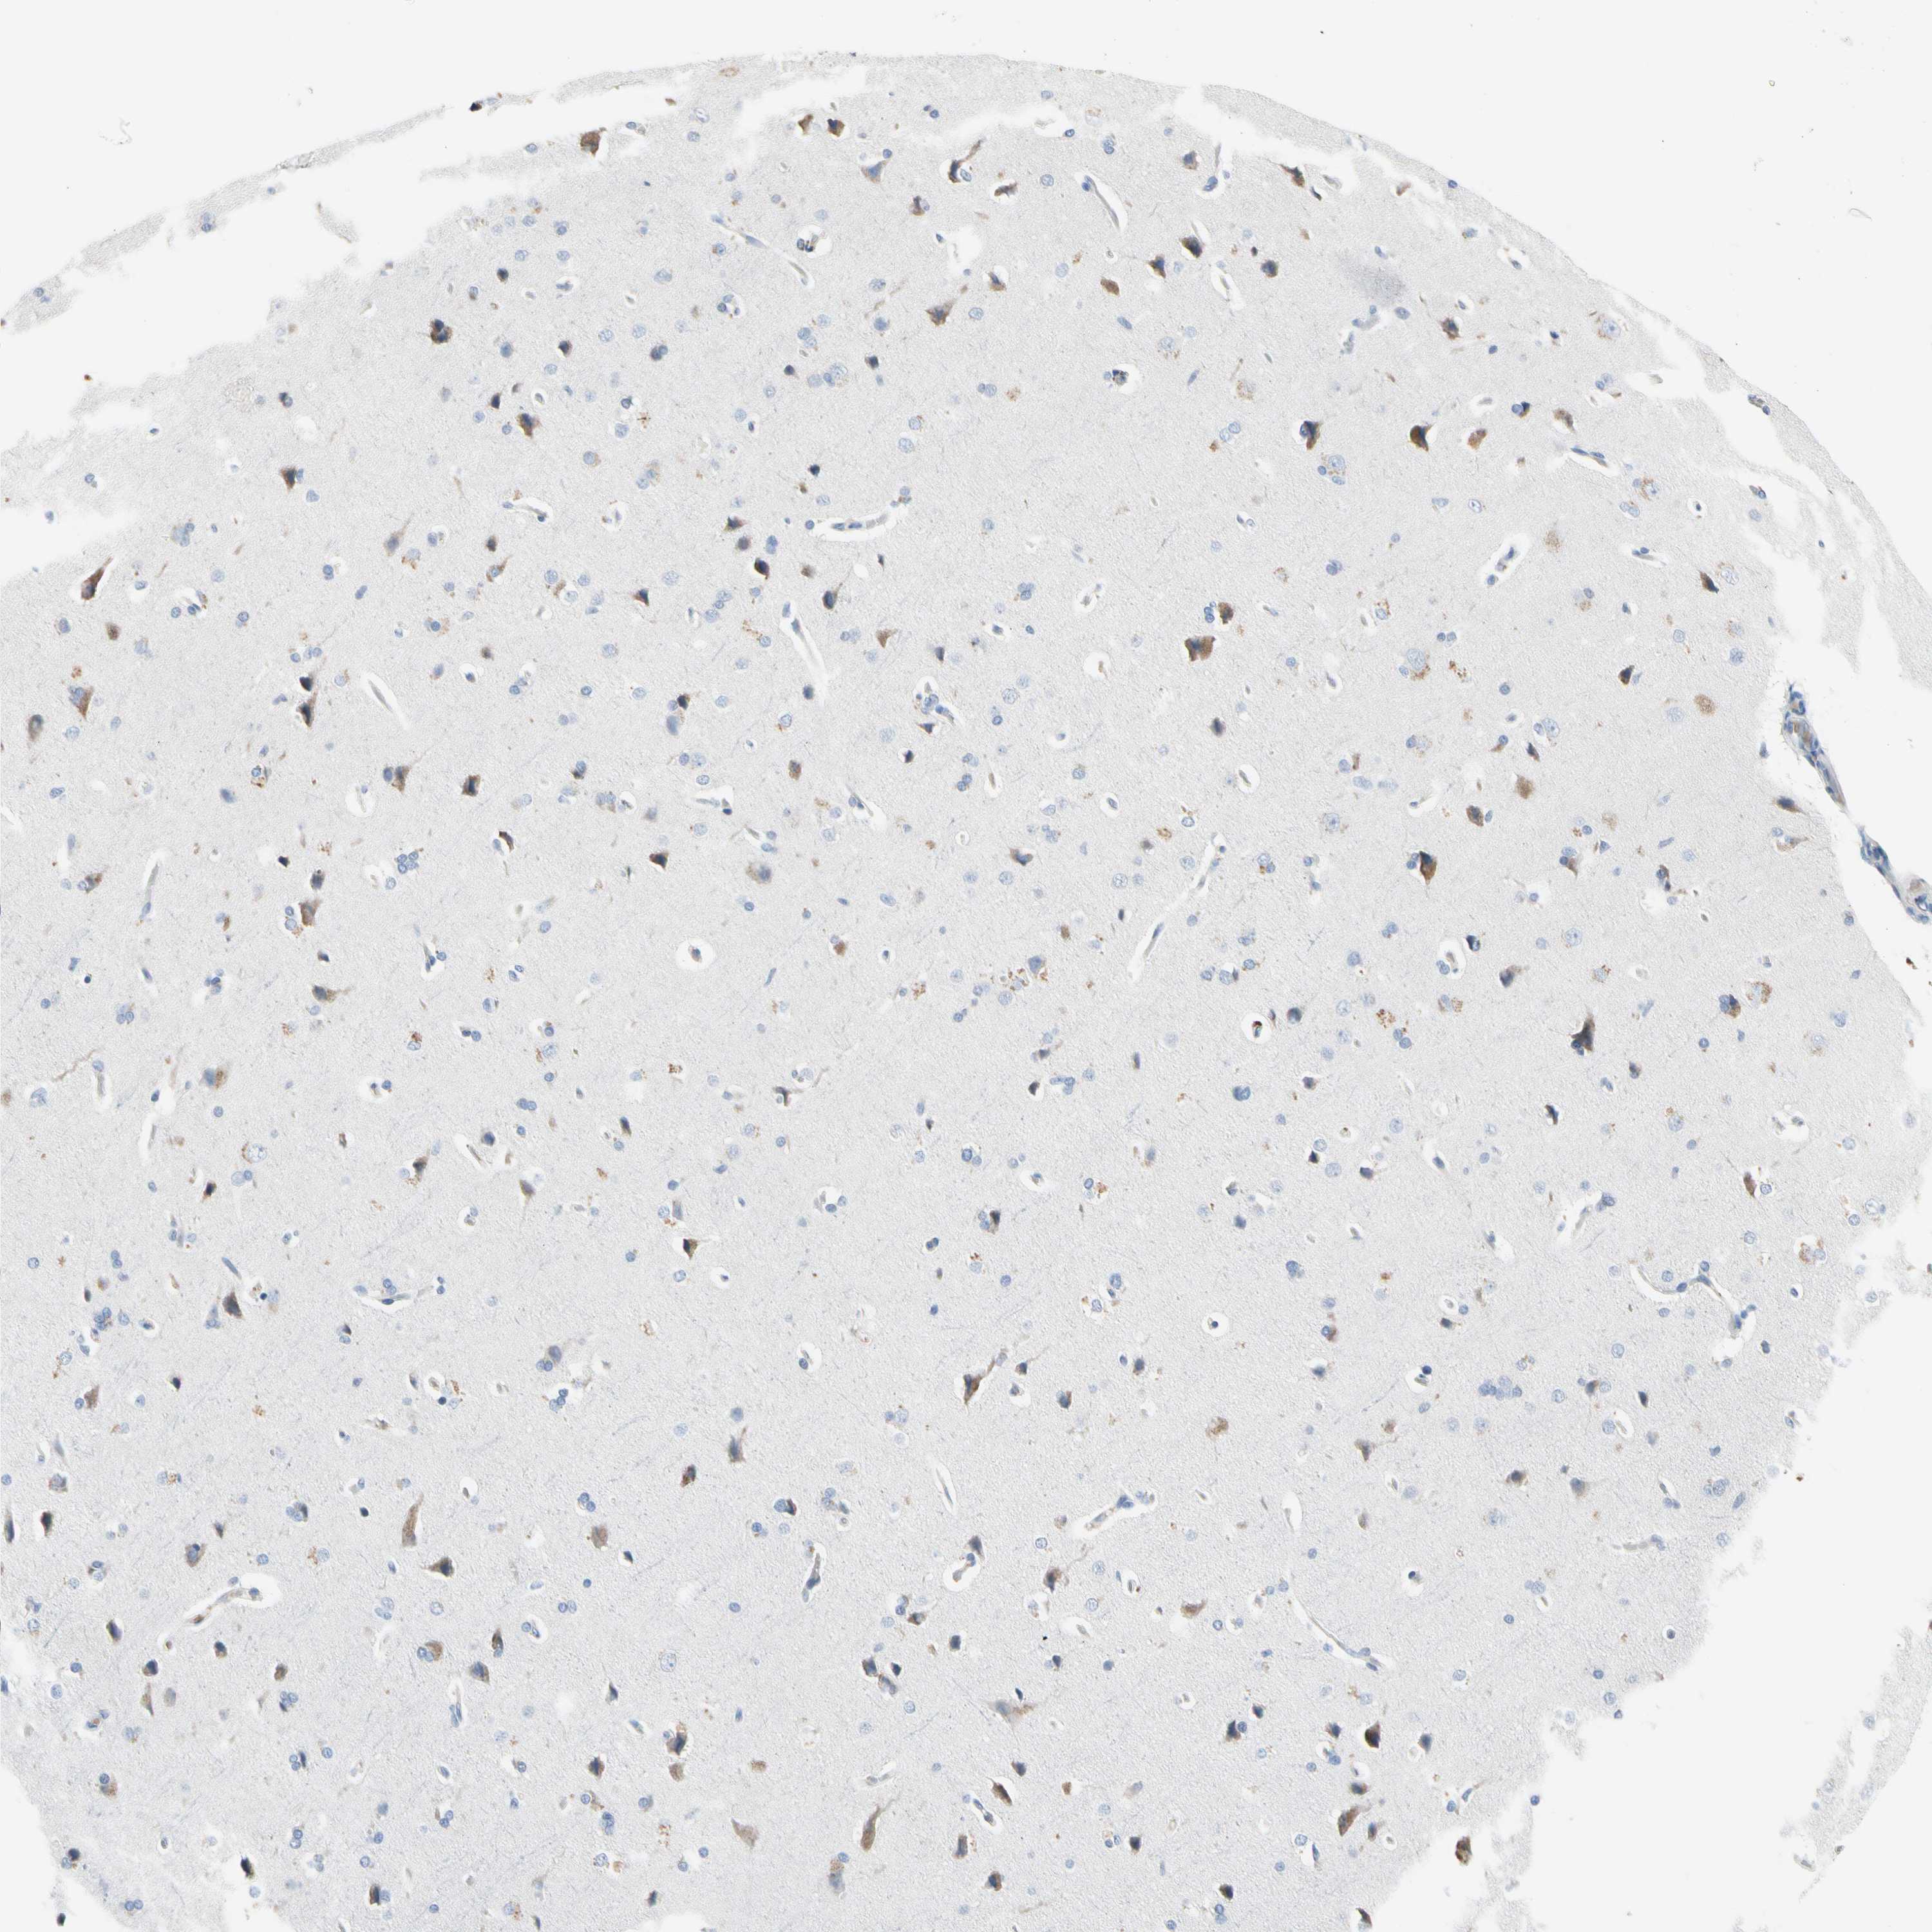

ECRG4